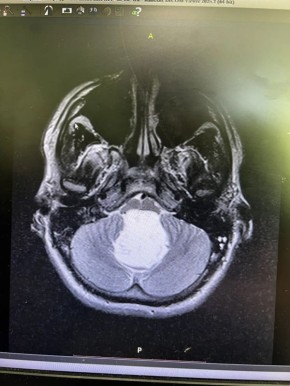

Никита был обычным крепким парнем: спорт, армия — причем в элитные войска, куда каждого второго не берут. Первые легкие головные боли появились еще в 2024-м, но кто на них обращает внимание в таком возрасте? К 2025-му голова разламывалась уже всерьез...